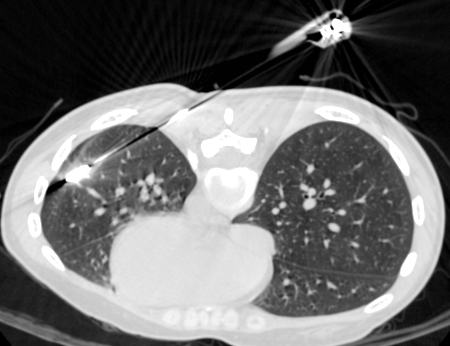

而患者不愿意接受外科手术切除,也不愿意长期随访观察,经过医患共同决策(Shared decision making,SDM),于手术当日,在CT引导下完成了“经皮穿刺”肺活检术及微波消融术,手术历时120秒,影像显示左肺0.8cm结节损毁,达到手术根治效果。

汪小舟介绍道,该患者病灶位置深,微波消融难度大,经过准确的定位,整个手术过程非常顺利,从准备到手术结束,仅耗时半小时,术中、术后病人几乎无任何痛苦。对于患者来说,“肺结节微波消融手术”无疑是一个新的治疗途径。

微波消融天线插入肺结节